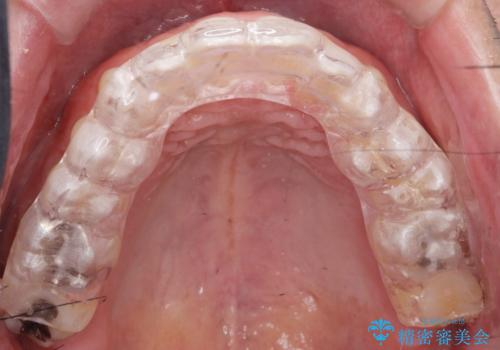

保険のナイトガードよりも穴が空きにくいナイトガードのご案内をしてフラットタイプナイトガード(自費でのご案内)

を作製することになりました。

- フラットタイプナイトガード 3.3万円費用は治療当時の料金となります

保険のナイトガードよりも厚くて硬いので壊れたり割れたりする心配がありません。

またナイトガードを装着して全体的に噛む力が均等になるように調整を行います。